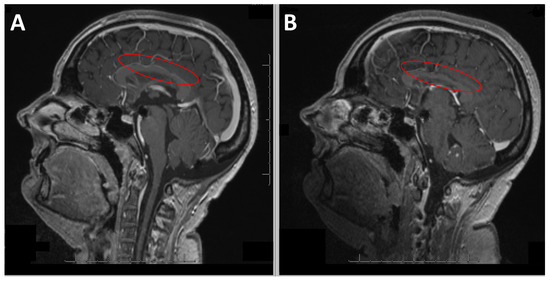

Remote imaging one month later showed signs of Wallerian degeneration extending to the splenium of the corpus callosum, the stable scalloped appearance of the corpus callosum, and the focal atrophy of the anterior corpus callosum and isthmus (Figure 2). PET imaging revealed mild cortical hypometabolism in the bilateral prefrontal and inferior parietal areas, sparing the sensorimotor cortex, and asymmetric cerebellar uptake favoring the left side. Three months after the transfer to the rehabilitation center, the patient returned home. A follow-up visit nine months after hospitalization showed favorable motor and functional progress. The oral dopaminergic treatment had been discontinued without worsening motor parkinsonian symptoms; the lack of motivation, or apathy, was likely due to lesions in the dopaminergic pathways from the ventral tegmental area to the limbic striatum and medial frontal cortex.

Figure 2. Case 1: (A) Sagittal T1-weighted MRI showing the undulating appearance of the corpus callosum (red oval on (A)) described as scalloping indicating a segmental ventral collapse between the branches of the pericallosal artery connecting the corpus callosum to the cingulate gyrus secondary to hydrocephalus after VP shunting. (B) Sagittal T1-weighted MRI showing atrophy of the corpus callosum (red oval on (B)).